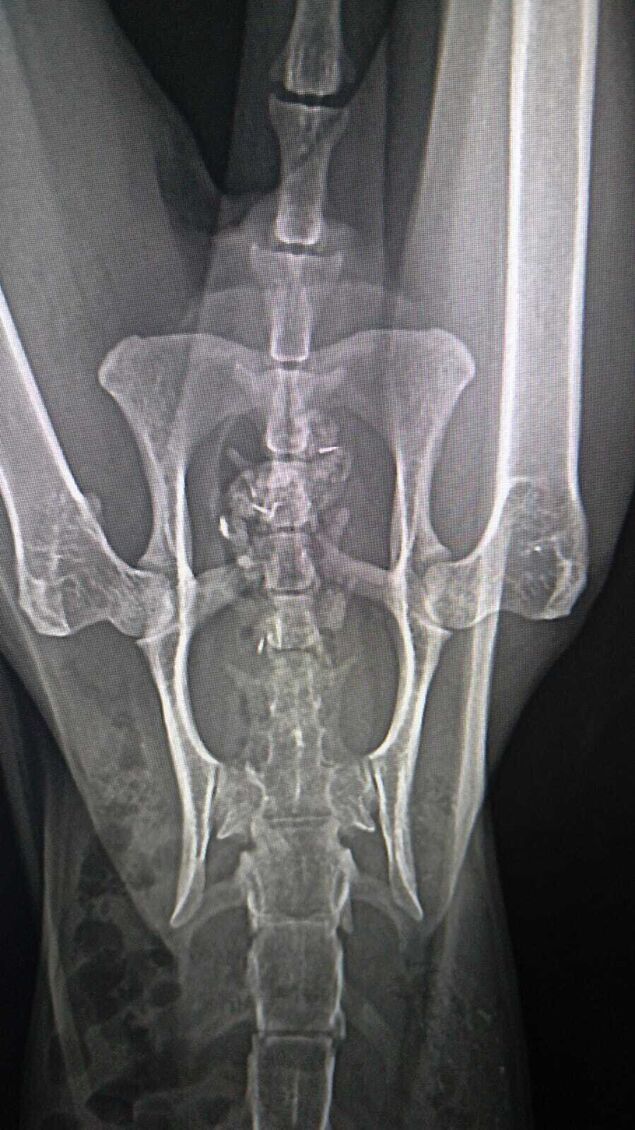

"Wenn wir das auf den Röntgenbildern nicht nachweisen könnten, glaubt uns das niemand", behauptet Birgit Block, Vorsitzende des Cuxhavener Tierheim-Vereins "Eine Pfote, ein Versprechen": "Es ist schier unglaublich, was dieser lieben Katze mitten in Cuxhaven widerfahren ist."

"Was bewegt Menschen, so etwas Grausames zu machen?", fragt Birgit Block empört. Denn eine aufgelesene Katze sei mit einer Schrotflinte angeschossen worden. Danach habe sich das Tier kaum bewegen können und auf seinen Tod gewartet. "In dieser Zeit des Wartens hat sie wahnsinnig abgebaut und sich ihr Sprunggelenk kaputt gelegen", berichtet die Tierschützerin.

Derzeit sei die Katze medikamentös abgedeckt. "Wir gucken, wie der Verlauf in den nächsten 14 Tagen ist. Von einer OP wird erst mal abgesehen, da es zu kompliziert wird", erklärt die Tierheim-Vereinsvorsitzende. Die Tierschützer würden sich freuen, "wenn wir einen Paten für diese zauberhafte Samtpfote finden könnten".